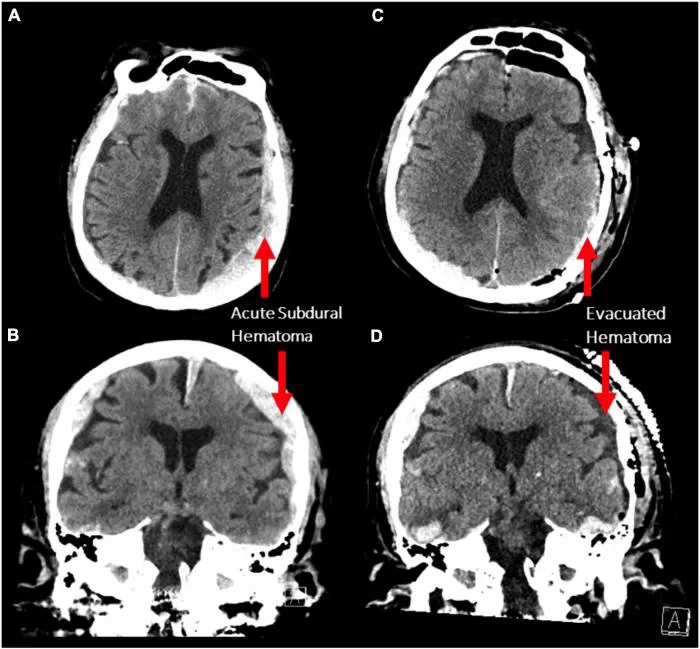

Cette étude, menée sur un patient de 87 ans épileptique, se base sur une électroencéphalographie (EEG) prévue pour détecter des crises. Seulement, le patient est décédé à la suite d'une crise cardiaque, permettant aux scientifiques d'enregistrer l'activité d'un cerveau humain mourant pour la toute première fois. Une "chance" dans ce malheur qui va permettre de faire avancer la science.